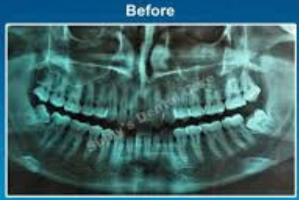

Tooth Extractions involve the removal of a tooth that is damaged, infected, or causing crowding. Impaction treatment refers to removing teeth (commonly wisdom teeth) that fail to erupt properly and cause pain or infections. Both procedures are done under anesthesia for comfort and safety.

Before & After Care